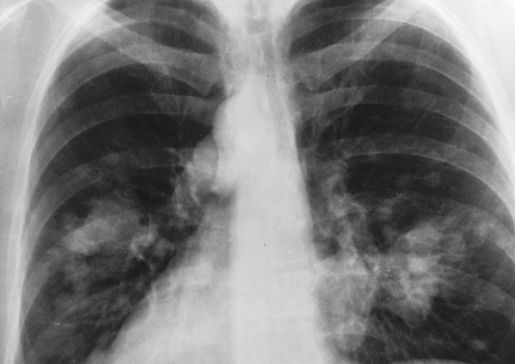

lung x-ray

Successful patient outcome in lung cancer clinical trial